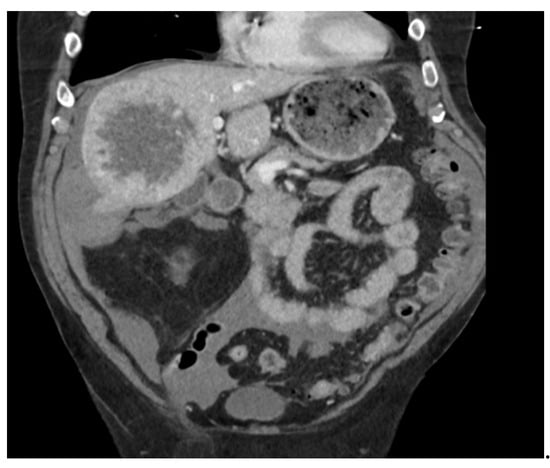

2. Case